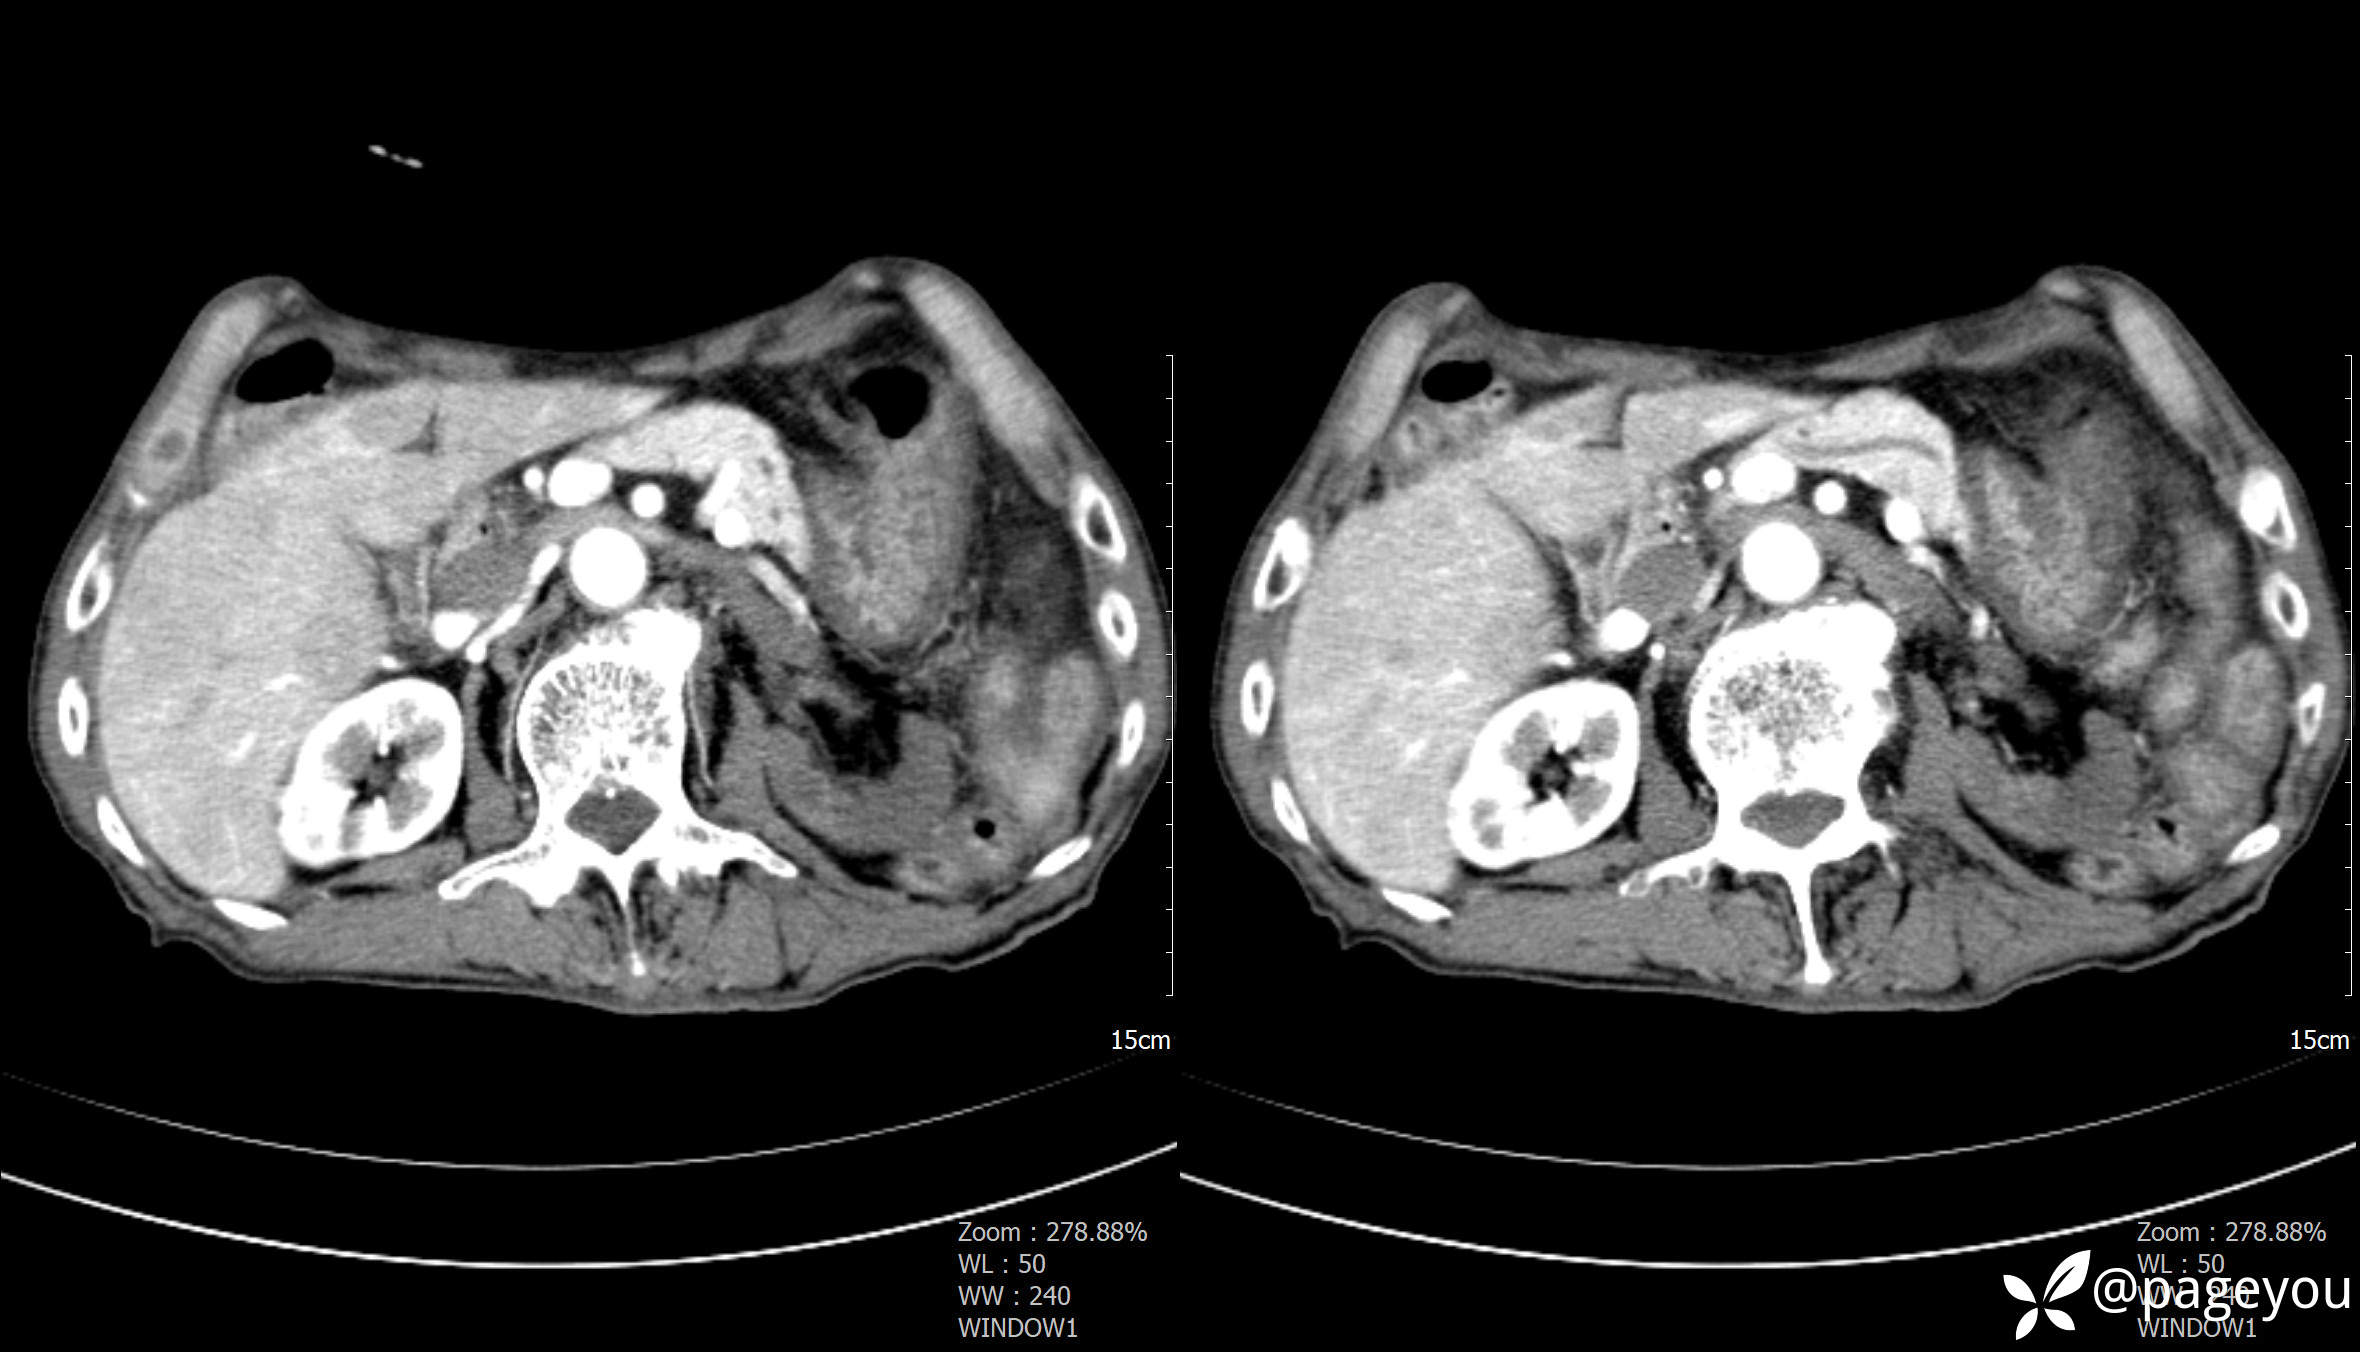

主动脉CTA: